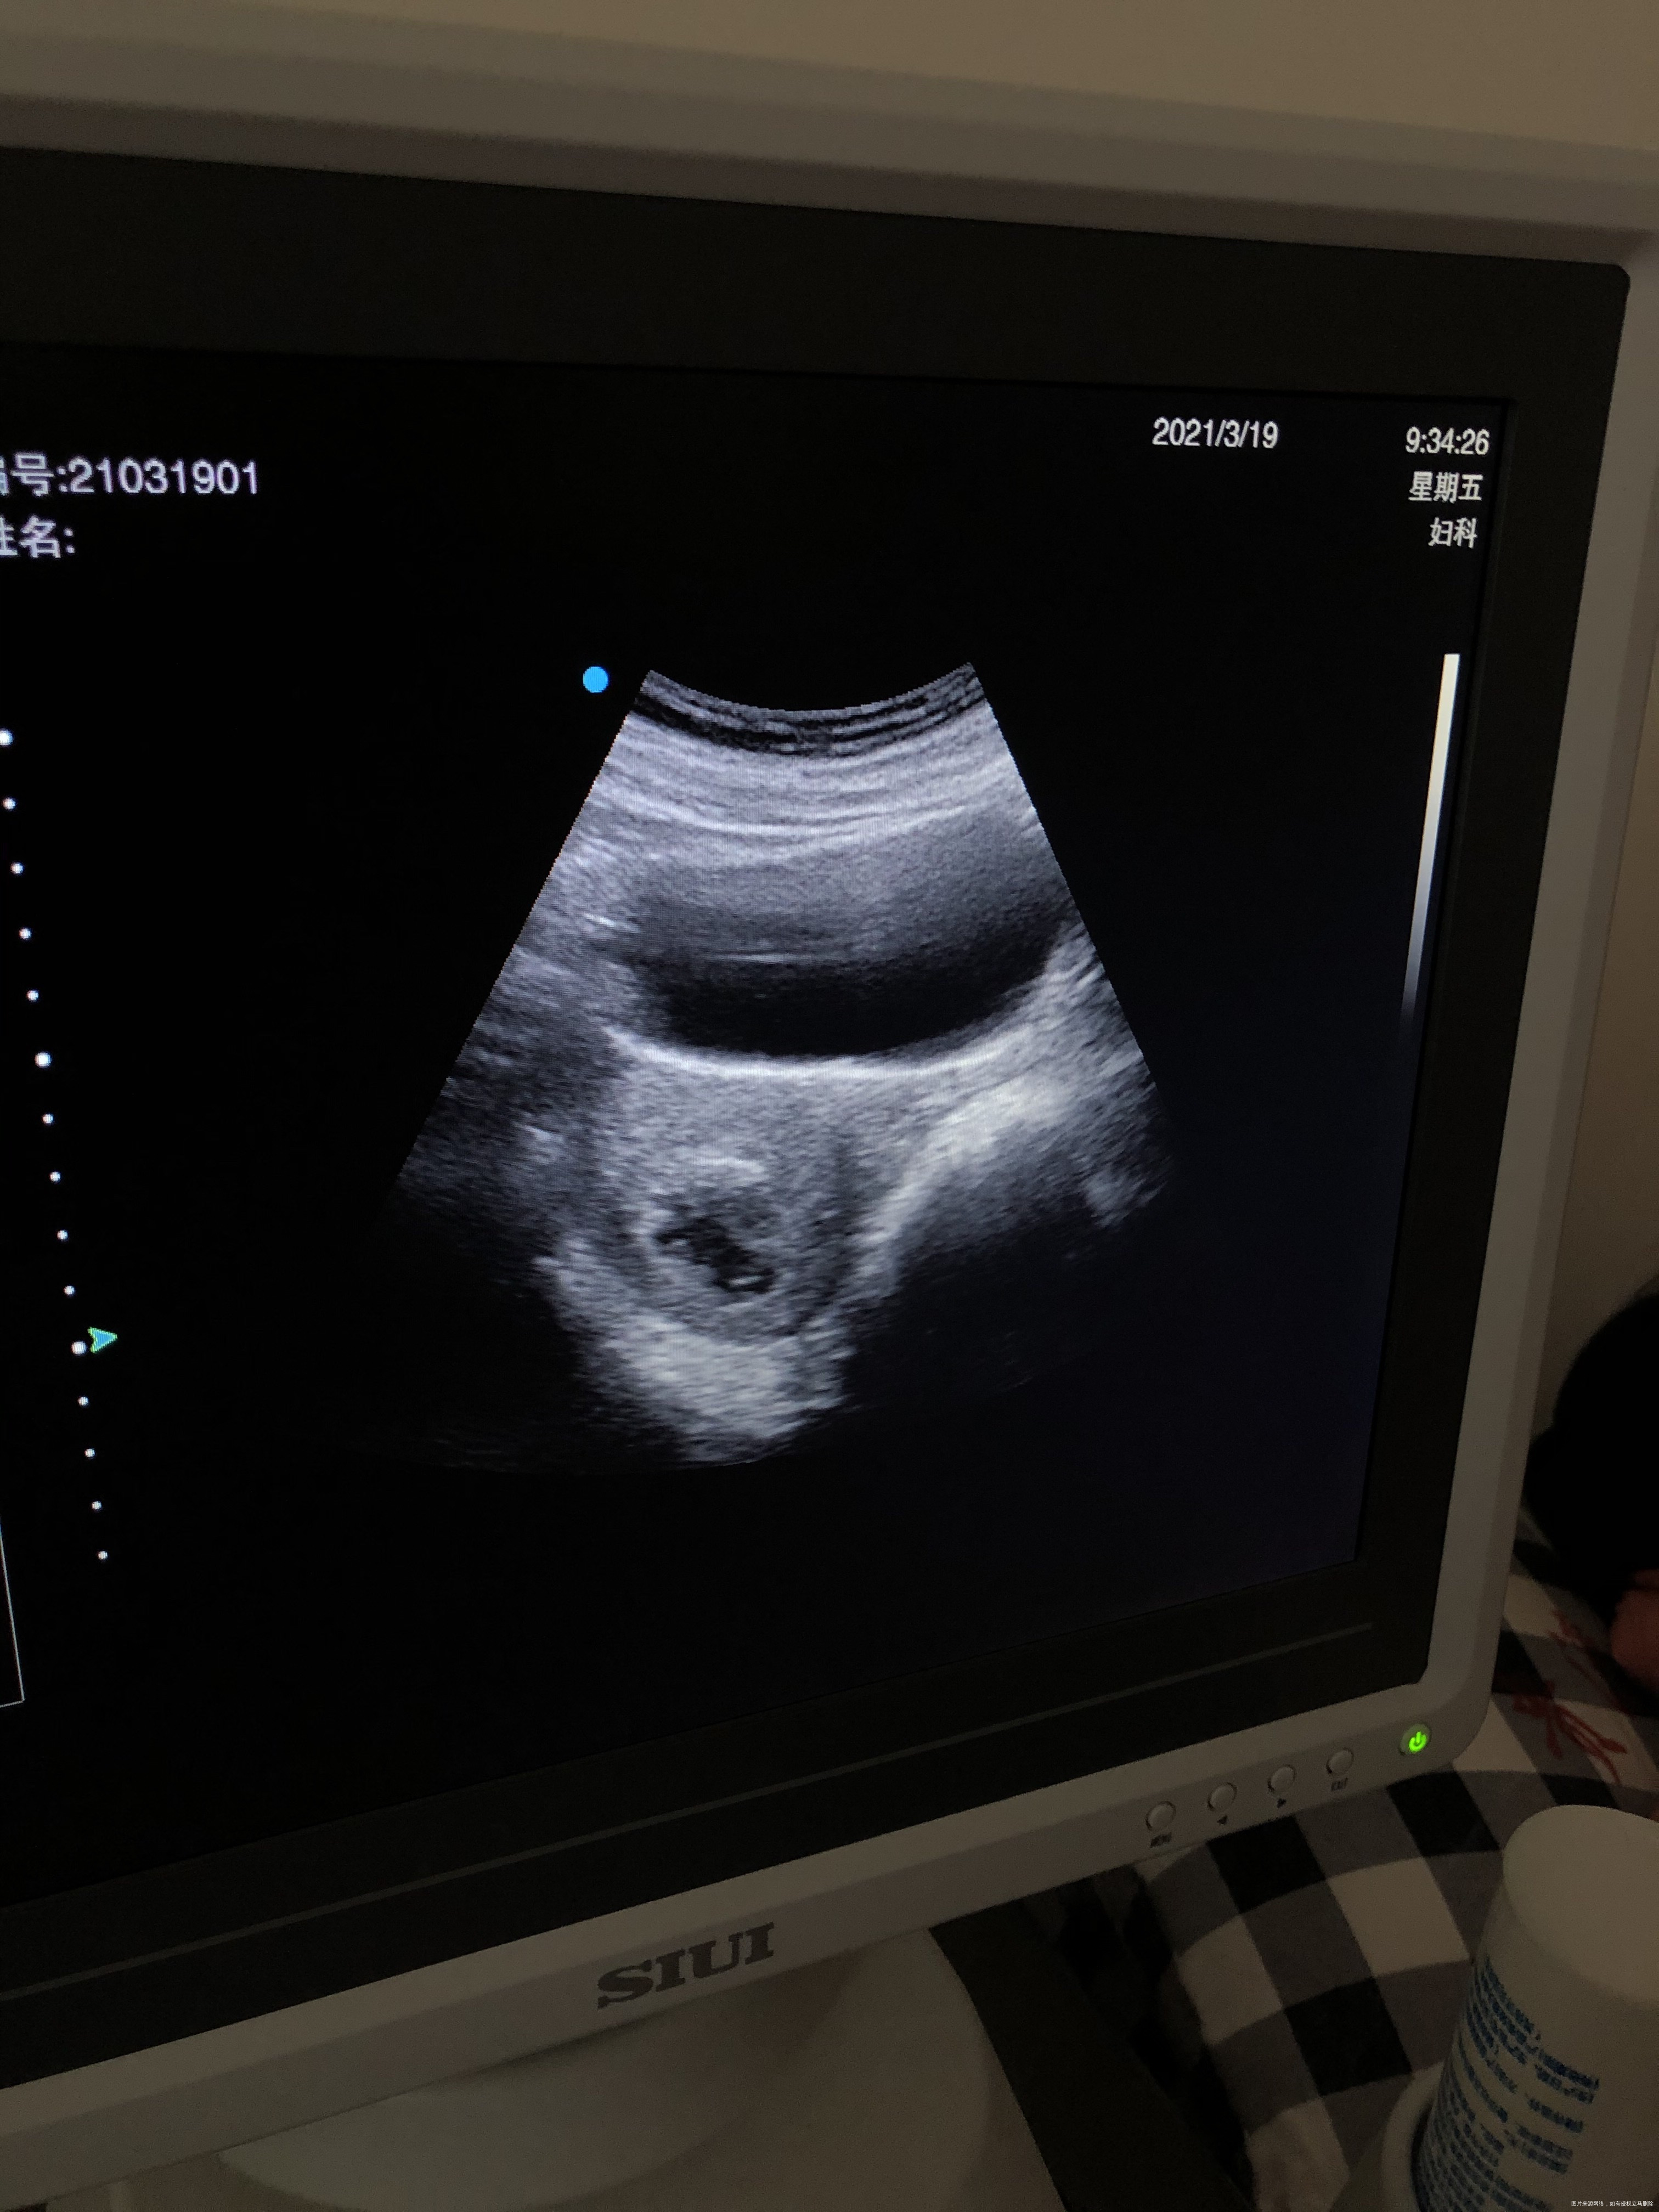

先解决这次出血问题,复诊看看彩超宫腔内膜情况。解决了再查胎停原因,双方一起查,35岁,胎停3次,先查双方染色体,也可以考虑三代试管

现在刮宫已经大约半个多月了,一般出血应该干净了,可以超声检查排除残留。本次干净后要先做夫妻双方染色体等检查,查找下胚胎停育的原因,针对原因进行治疗。

亲,一直不干净的话考虑有残留可能,复查彩超看下